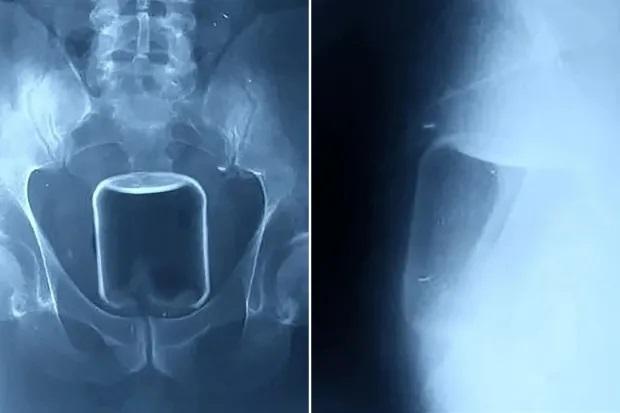

俄羅斯一名男子將500毫升的玻璃瓶塞進肛門。(互聯網)

從報道顯示的X光片看見,體積不細的玻璃瓶在肛門內較高位置,醫生最後成功取出它,連帶一個安全套。報道稱,那男子將一個容量500毫升的玻璃瓶塞進肛門,並將其推進腸道,最後因無法取出而求醫。俄羅斯下諾夫哥羅德一間醫院公開有關個案,稱醫生非道德警察,不會評論病人非傳統的性傾向,呼籲民眾若遇相同情況,須尋求醫療協助。